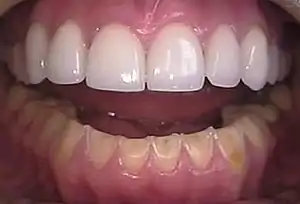

The erosion on the lower teeth was caused by bulimia. For comparison, the upper teeth were restored with porcelain veneers.[11]

People with bulimia are more likely than people without bulimia to have an affective disorder, such as depression or general anxiety disorder. One study found 70% had depression at some time in their lives (as opposed to 26% for adult females in the general population), rising to 88% for all affective disorders combined.[25] Another study by the Royal Children's Hospital in Melbourne on a cohort of 2,000 adolescents similarly found that those meeting at least two of the DSM-IV criteria for bulimia nervosa or anorexia nervosa had a sixfold increase in risk of anxiety and a doubled risk for substance dependency.[26] Some with anorexia nervosa exhibit episodes of bulimic tendencies through purging (either through self-induced vomiting or laxatives) as a way to quickly remove food in their system.[27] There may be an increased risk for diabetes mellitus type 2.[28] Bulimia also has negative effects on a person's teeth due to the acid passed through the mouth from frequent vomiting causing acid erosion, mainly on the posterior dental surface.